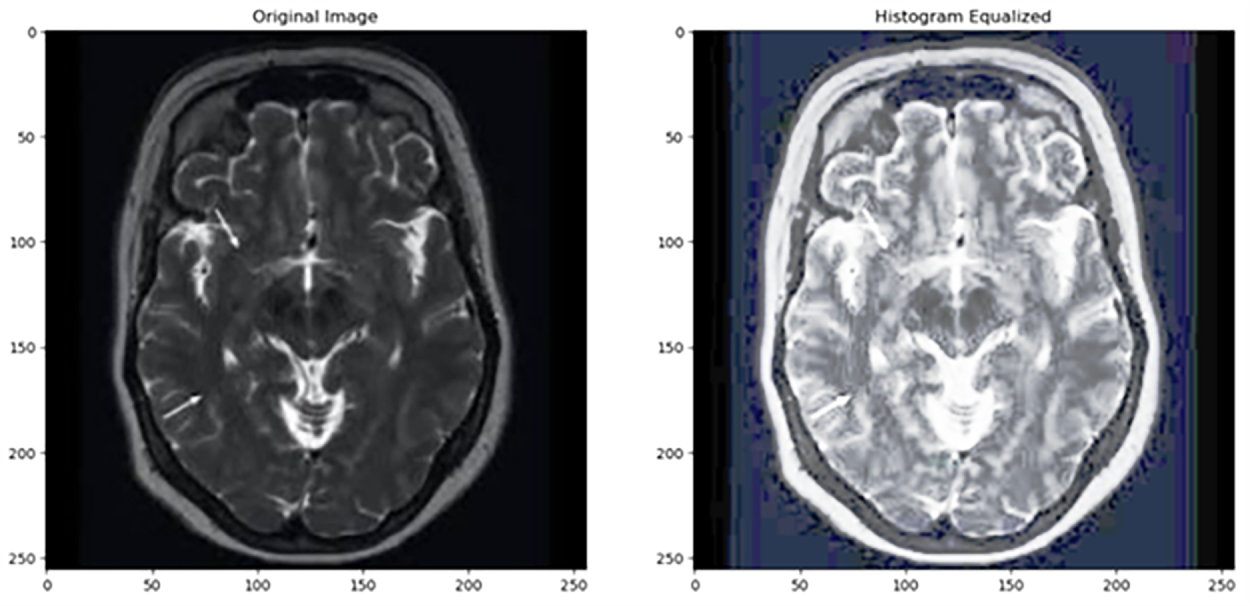

Histogram Equalization (HE) is a spatial domain technique. It increases contrast, improves image quality, and enhances the visibility of features in MRI brain images [3]. It is widely used and is one of the simplest methods for contrast enhancement. For instance, the authors in [10] compared histogram equalization and filtering techniques for medical thermal imaging in breast cancer detection. They found that while histogram equalization enhances contrast, it skews the temperature profile, that is a fundamental aspect for diagnosis, and potentially resulting in misinterpretation. Since filtering methods such as Wiener filtering preserve the original temperature information, they are more appropriate for accurate clinical analysis. Fig. 2 shows that histogram equalization (HE) can lead to over-enhancement, resulting in exaggerated contrast in certain regions of the image. Recently in 2022, Histogram Equalization with Minimum Cross-Entropy-Otsu [11] was proposed; it enhances medical image contrast while preserving brightness, improving diagnostic quality with low computational complexity, but it may not handle very noisy images.

Table 1 provides a quantitative comparison between the original and histogram-equalized image from Fig. 2. The equalized image shows a very low PSNR (8.82 dB) and SSIM (0.366), indicating substantial distortion and low similarity to the original. Although both images have the same contrast index (1.00), entropy slightly decreases after equalization (from 6.13 to 5.94), suggesting a small loss in information content. Overall, these metrics confirm that histogram equalization, while enhancing contrast, significantly degrades image quality and alters its statistical properties.

Figure 2: As shown in this figure, histogram equalization introduces excessive contrast in homogeneous regions. Source: Kaggle dataset [4].